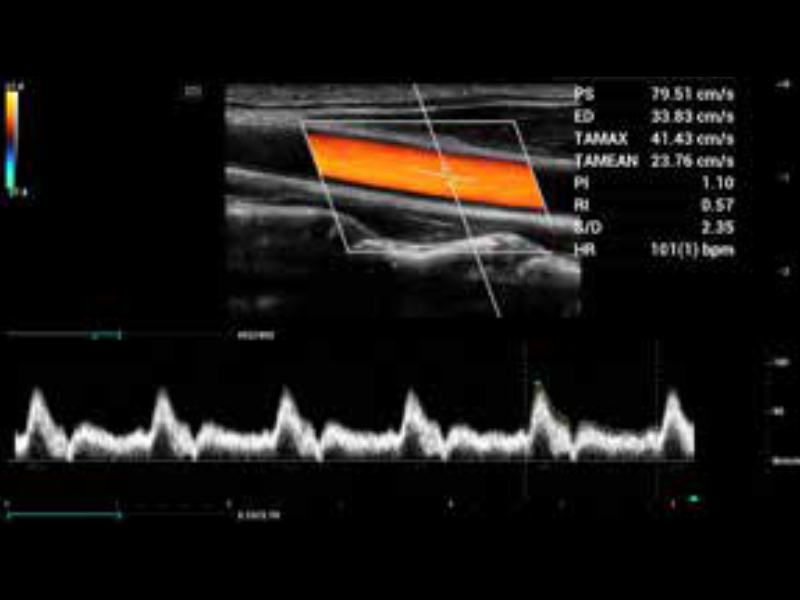

AutoCalc + Smart Track

Istotne jest, aby śledzić pozycję naczyń, używać odpowiedniego kąta oraz dopasowanej wielkości bramki dopplerowskiej. Smart Track robi to automatycznie.

• zeus-fig5-3-1-uk

Doppler tętnicy szyjnej z automatycznymi obliczeniami

• zeus-fig5-3-2-uk

Tętnica szyjna i żyła szyjna